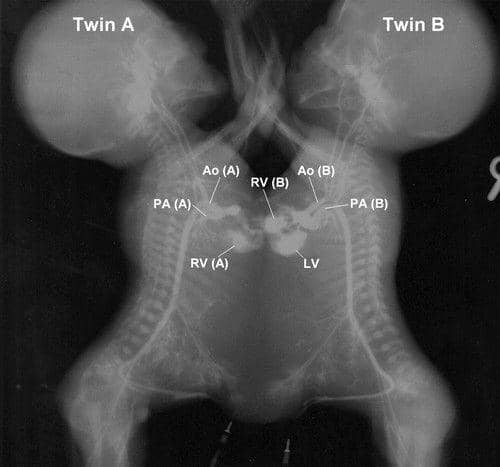

Ada lebih dari selusin klasifikasi untuk kembar siam berdasarkan di bagian tubuh mana mereka terhubung. Yang paling umum adalah thoracopagus twins, yaitu 37 persen dari seluruh kembar siam yang ada di dunia.

Jenis kembar siam ini terhubung di dada bagian atas dan berbagi hati yang sama. Itulah kenapa pemisahannya hampir tidak mungkin bisa dilakukan.